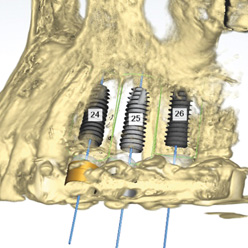

STEP2

임플란트 식립경로 확보

3D 디지털 보철 디자인

개별 맞춤형 수술 유도장치 디자인